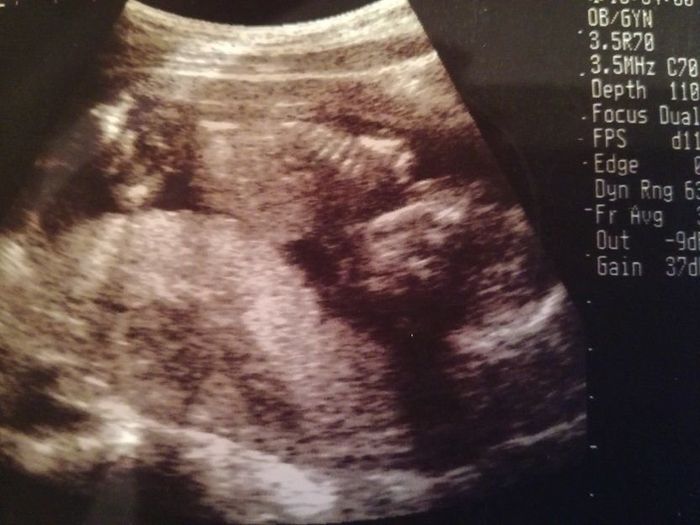

妊娠6週目のエコー写真

薄茶色のおりもの(出血)があり、気になって産院へ電話。「とりあえず、診察へ」と言われて受診しましたが、妊娠初期によくある程度の出血だから大丈夫とのこと。出血止めの薬だけ処方されました。ちょうどこの時、エコーで白い小さな粒を確認。「これが赤ちゃんに成長していきます」と先生に聞いて、愛しさでエコー写真をしばらく眺めていました。夫に見せたら、「ちっこい」と笑っていました。